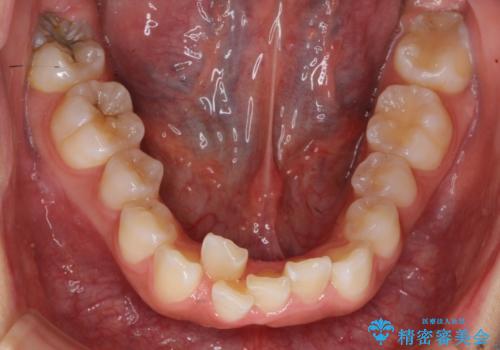

前歯のがたがた 前歯が内側に傾いている

- 前歯のがたがたを主訴に来院。